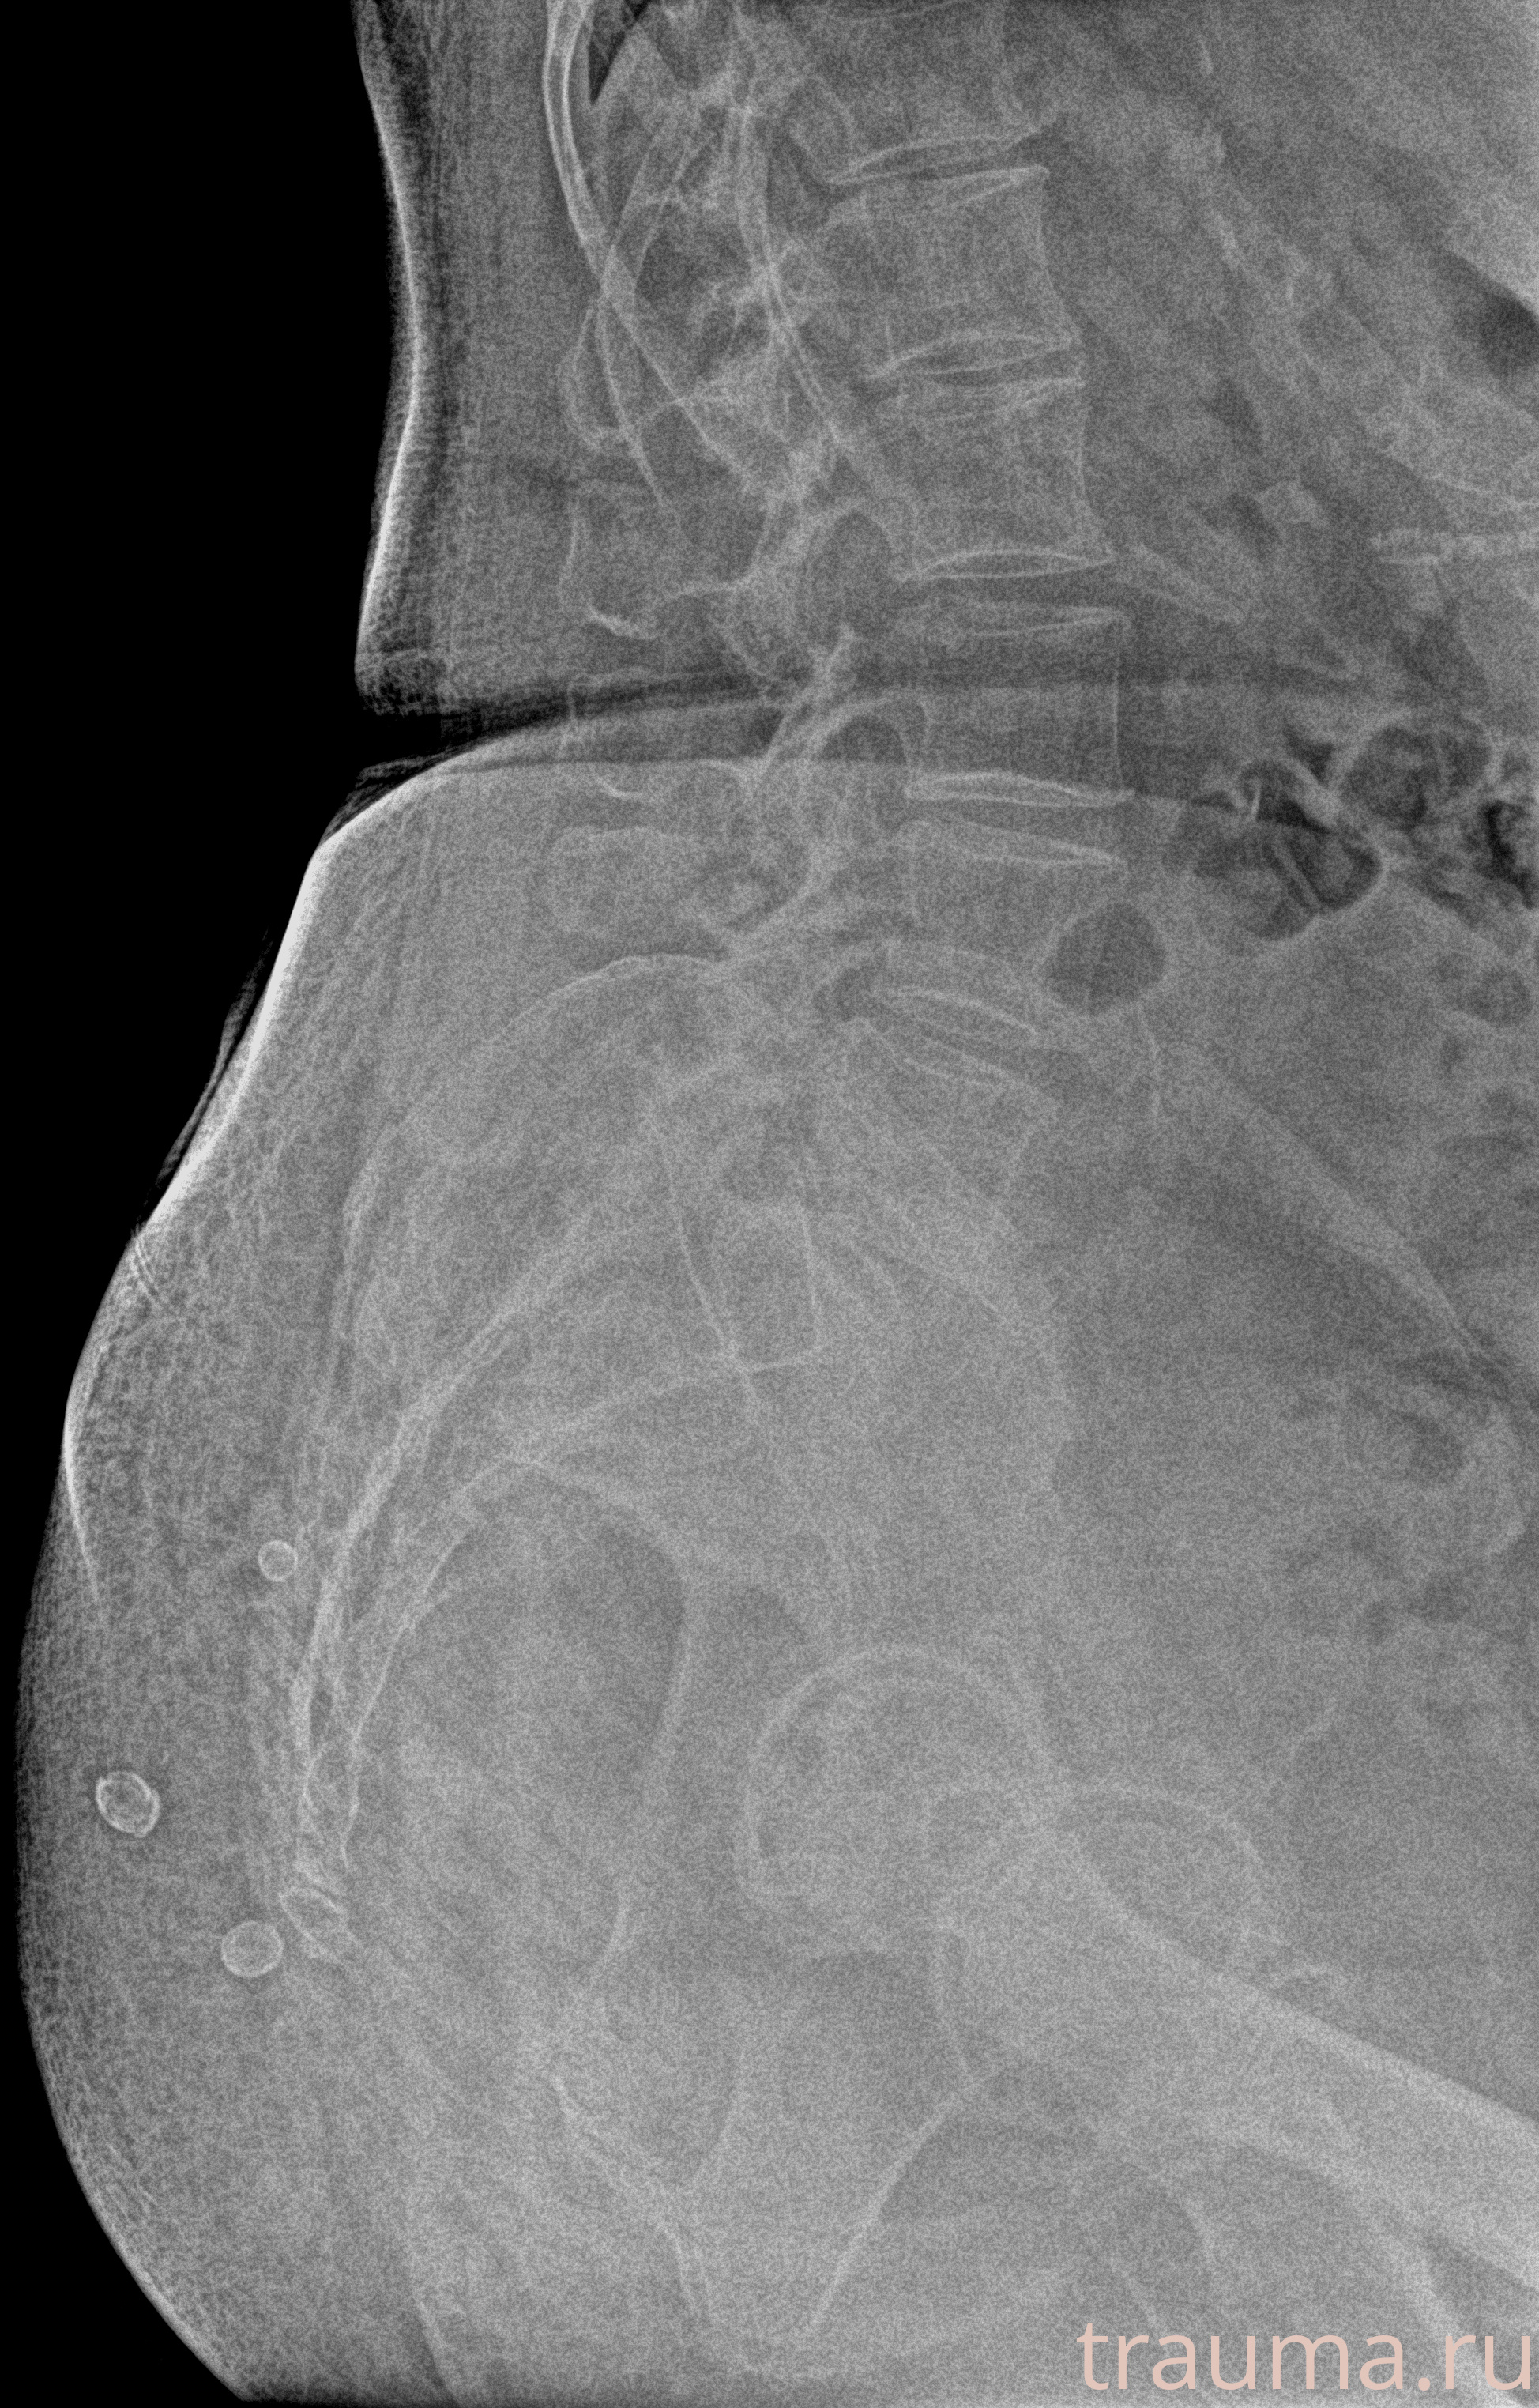

Рентгенограммы

Рентген на дому: по вашему адресу приезжает врач-рентгенолог, травматолог-ортопед с мобильным рентгеновским аппаратом, проводит диагностику травмы или заболевания, делает необходимые рентгенограммы, дает рекомендации по дальнейшему лечению. Получить качественные снимки в домашних условиях возможно благодаря уникальной методике, разработанной МосРентген Центром для института  Склифосовского